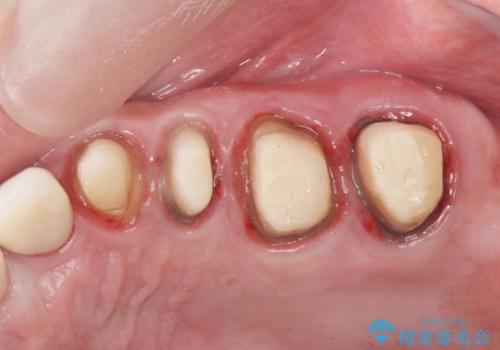

虫歯の徹底的な除去やセラミック補綴、精密根管治療、歯周外科を行うことで、治療後に歯磨きがしやすく、かみやすい機能的な仕上がりへと導きます。

歯周外科手術をおこなったことでフェルールも獲得でき、破折リスクをより抑えることにも成功しています。